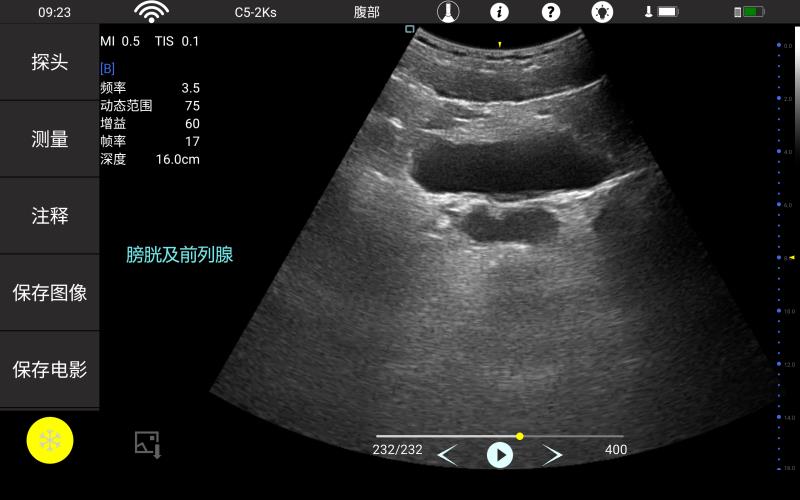

腹部

肾脏